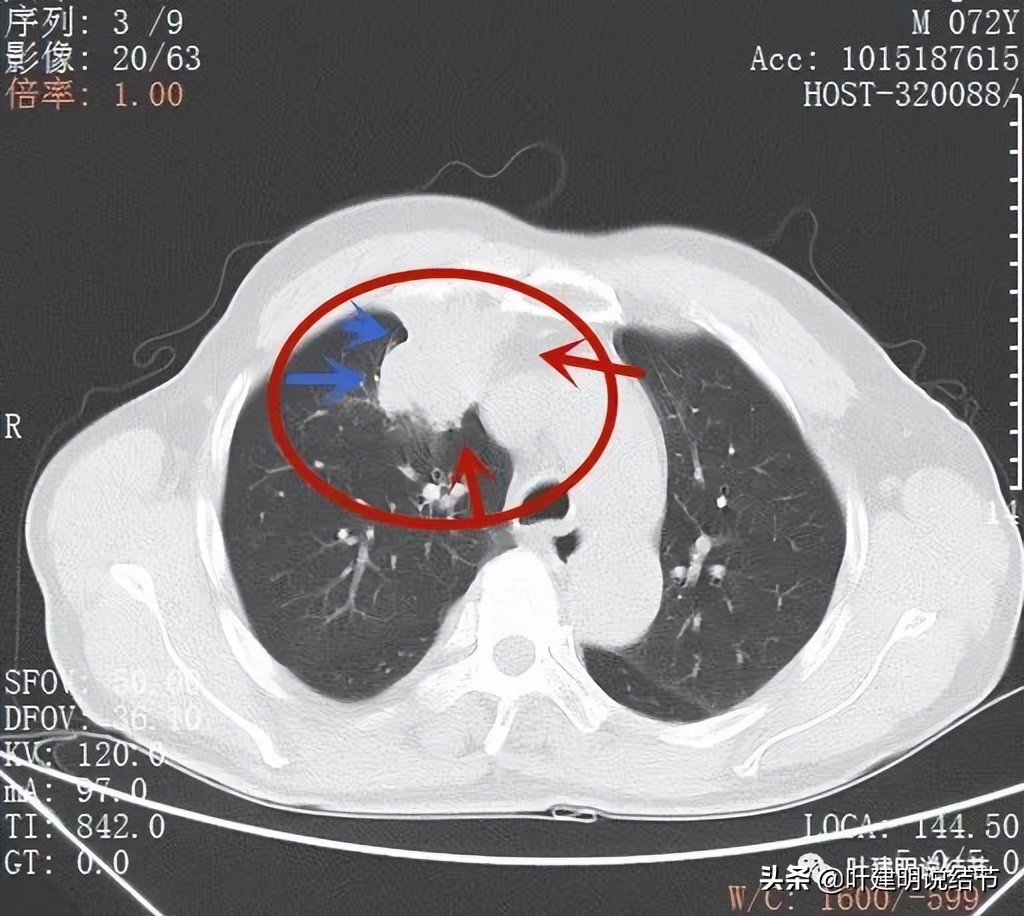

肿瘤位于上叶,实性,此层感觉有膨胀性;但边缘毛刺是不明显的,感觉偏光滑了点(蓝色箭头)

纵隔侧病灶没有推压纵隔组织,边缘相对平直(红色箭头),胸肋侧也是边缘较为光滑(蓝色箭头)